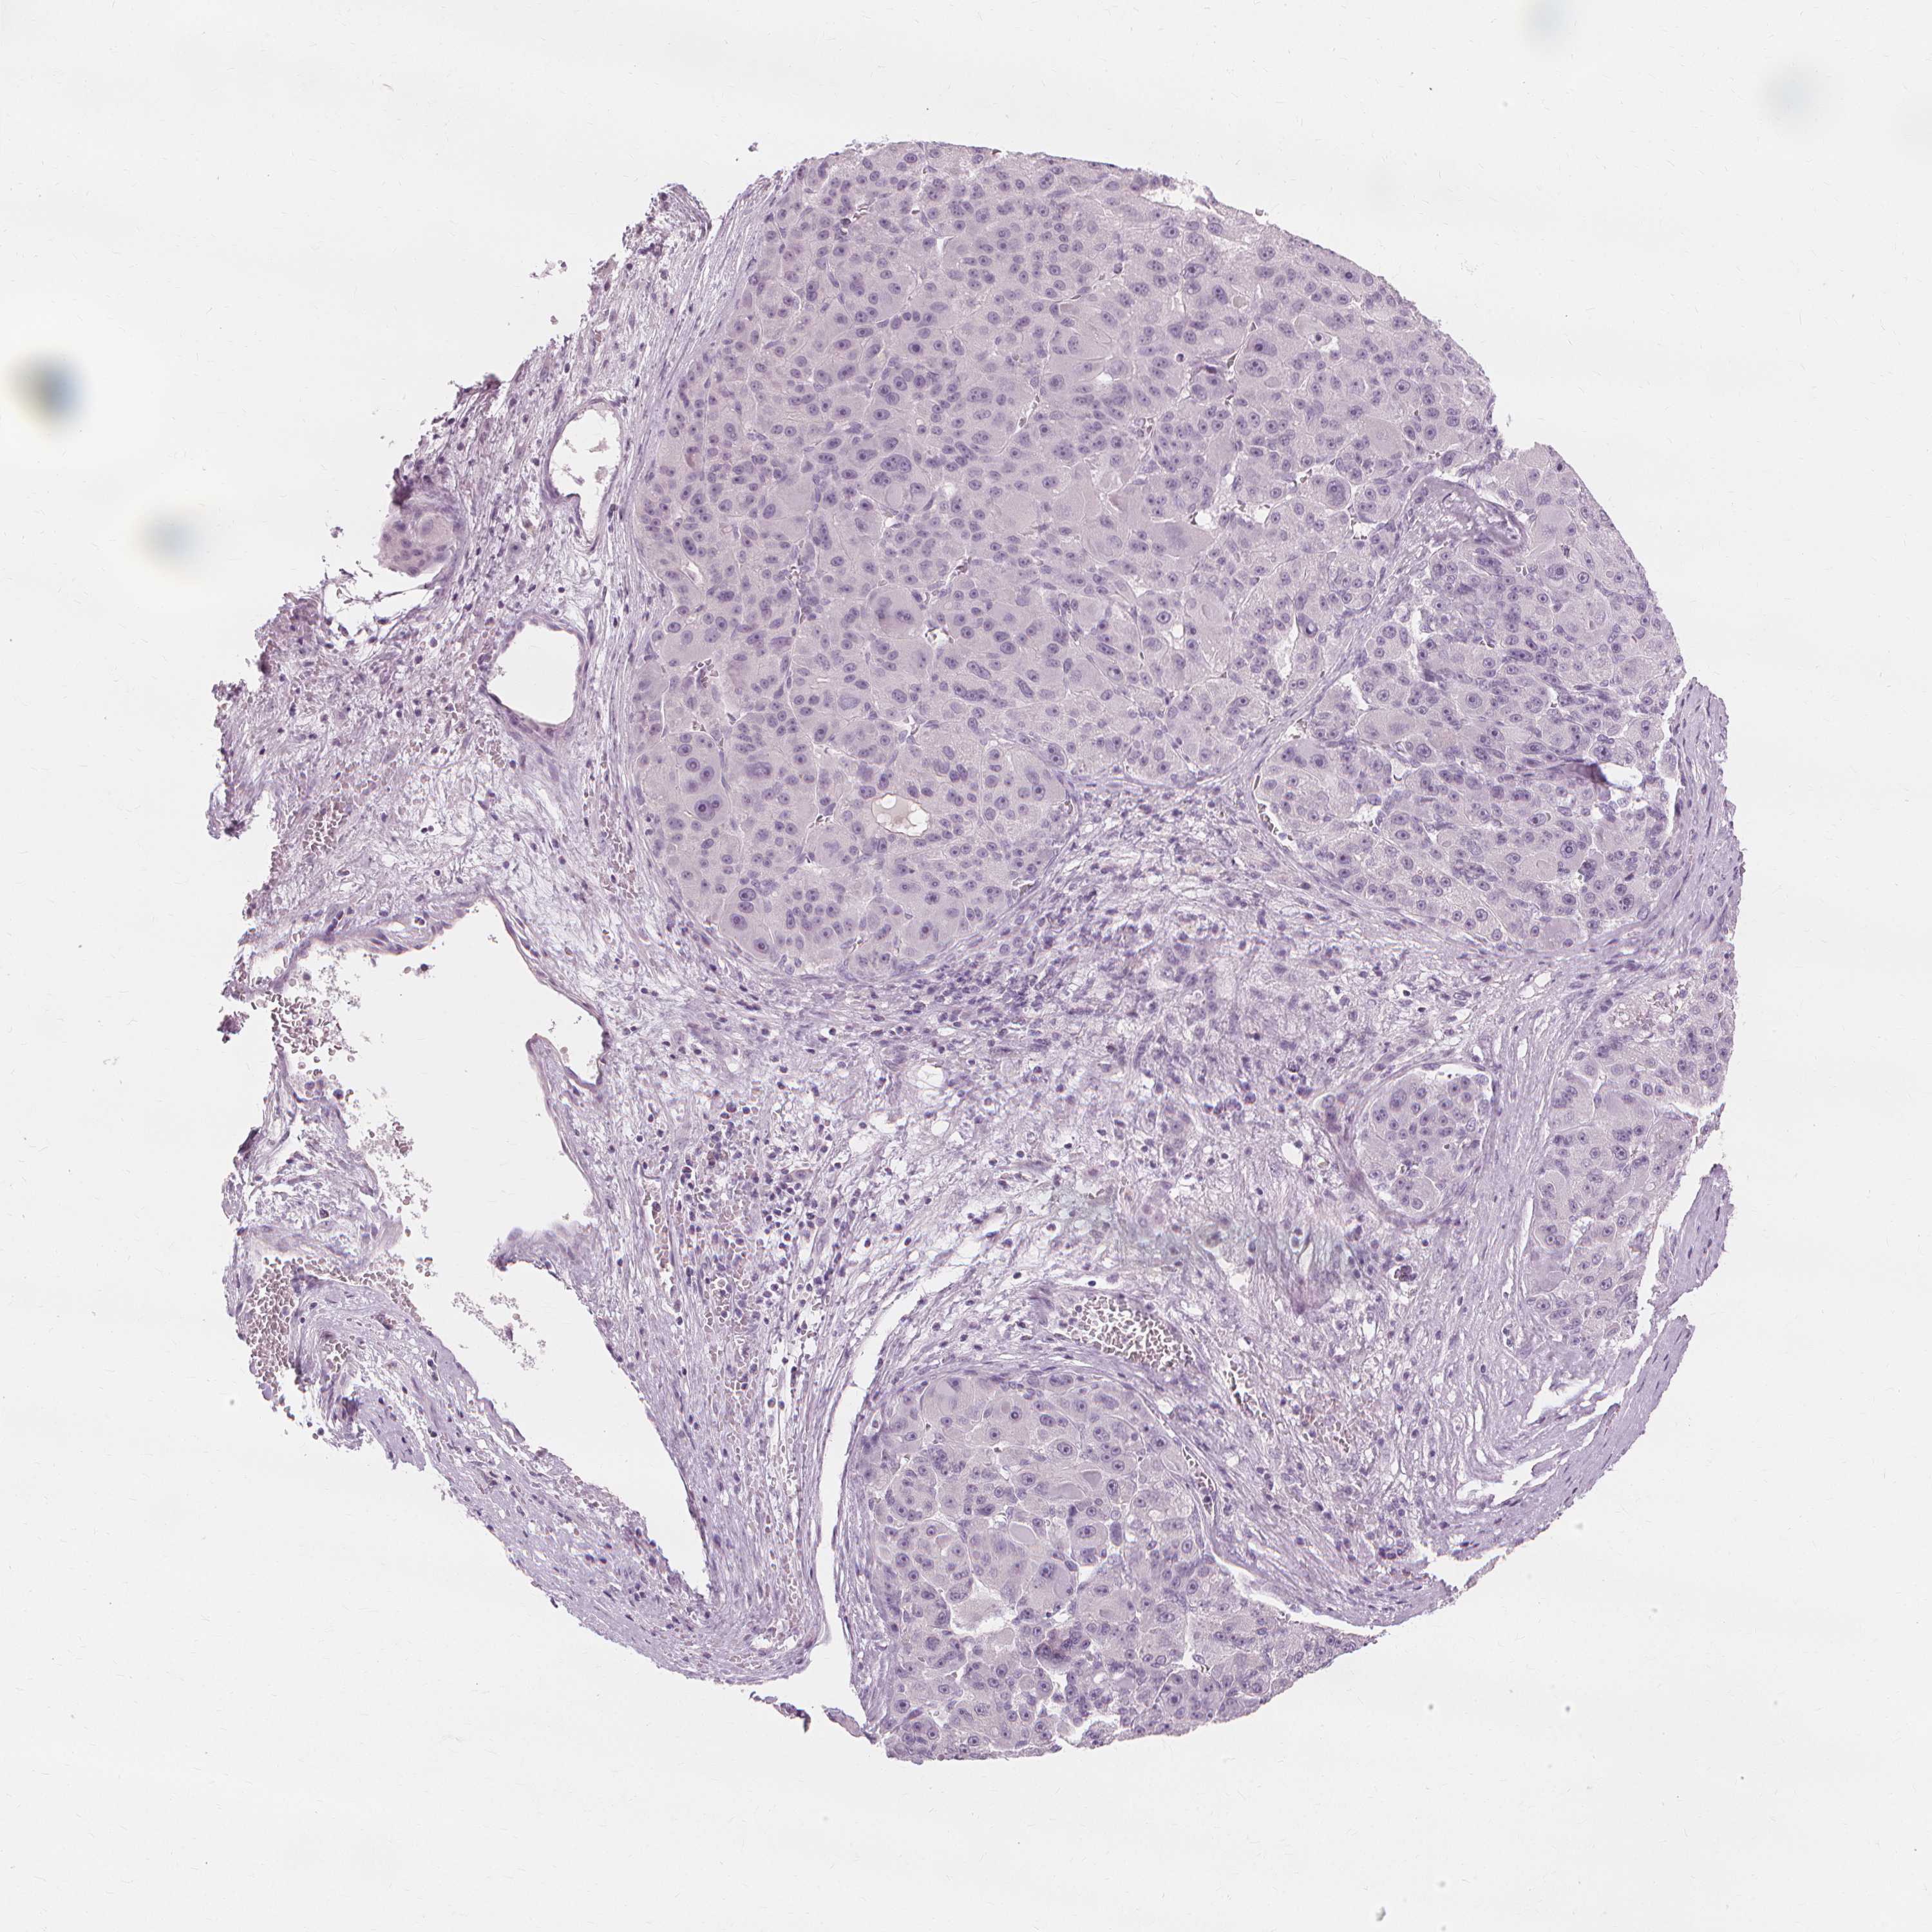

LIVER CANCER - Protein expressioni

A mouse-over function shows sample information and annotation data. Click on an image to view it in a full screen mode. Samples can be filtered based on level of antibody staining by selecting one or several of the following categories: high, medium, low and not detected. The assay and annotation is described here.

Note that samples used for immunohistochemistry by the Human Protein Atlas do not correspond to samples in the TCGA dataset.

Antibody stainingi

Antibody staining in the annotated cell types in the current human tissue is reported as not detected, low, medium, or high, based on conventional immunohistochemistry profiling in selected tissues. This score is based on the combination of the staining intensity and fraction of stained cells.

Each image is clickable and will lead to virtual microscopy that enables deeper exploration of all samples and also displays staining intensity scores, fraction scores and subcellular localization as well as patient and tissue information for each sample.

Antibody HPA023835

Staining

High

Medium

Low

Not detected

Intensity

Strong

Moderate

Weak

Negative

Quantity

>75%

75%-25%

<25%

None

Location

Nuclear

Cytoplasmic/membranous

Cytoplasmic/membranous,nuclear

Carcinoma, Hepatocellular, NOS

Cholangiocarcinoma